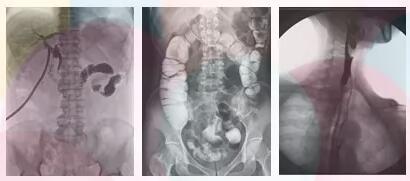

方面三、子宫输卵管造影,优选动态平板dr

采集面积大,一次曝光即可显示整个盆腔,大幅减少观察时间,可控的瞬时照射避免受检者吸收过多的X线,对育龄期妇女的检查尤为重要。实时高清点片,可以在造影剂流动的过程中完成拍片,抓拍到关键图像,清楚的了解管腔的具体通畅情况及堵塞部位,对检查及诊断有非常重要的价值。